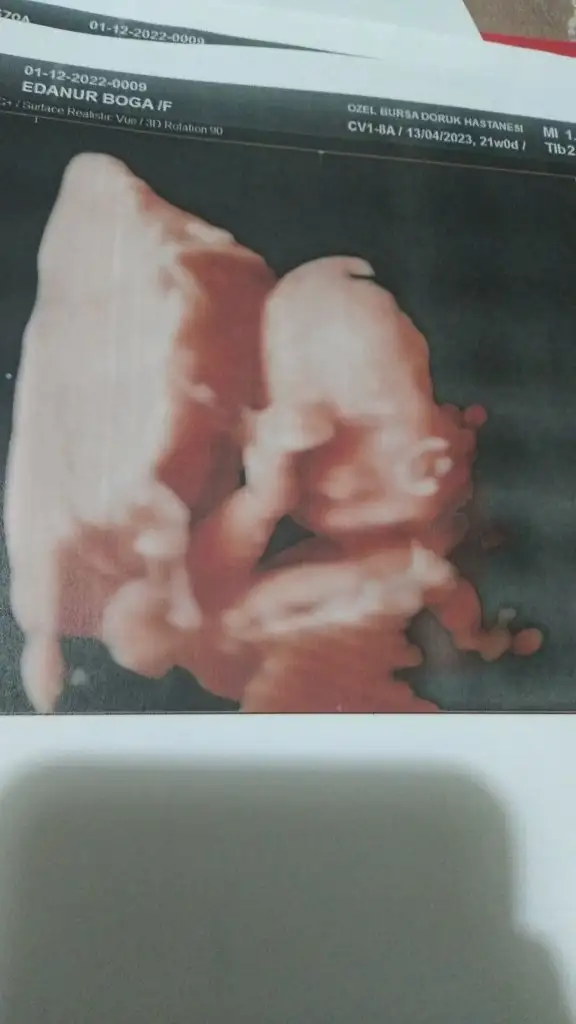

Evet 22 haftadayim canim bir ayagi yuzunde bir eli kulagindaydi doktor kiz dedi sasrdm beklemyodum cunku hemde nazli bi kiz dedi 3 kutu meyvesuyu ixtm cikolata yedim ara verdiler 15 dakka yurudum tekrar bakti usg kagifina kiz yazmis benm saliya randevum var simdi ozmnda sorayim en iysimuhtemelen daha 20. haftalardasınız daha bir süre alışveriş yapmaya bilirsiniz ama ayrıntılı ultrasonda net görünür diye düşünüyorum ya da emin olmak için başka bir dr a daha sorun cinsiyeti ben öyle yaptım gittiğim bütün dr lara sordum kesin kız mı diye en son dr bana usg de bebeğin vajinal bölgesini gösterdi çokta net görünüyordu artık emin oldum

22 hafta canim hatta serviks kisalms desi bana 38 miş bebegin el ayak parmaklarini beraber saydik renkliydi ztn esnerken bile gordüm ilk defa11de kız denmisti 2. Cocugumda ama erkekdi. Digerlerinde yanilinmadi. Haftasi buyukse bellidir bence. Erken haftalarda yanilma daha cok oluyor.

Bence degismez artik buyukmus.22 hafta canim hatta serviks kisalms desi bana 38 miş bebegin el ayak parmaklarini beraber saydik renkliydi ztn esnerken bile gordüm ilk defa